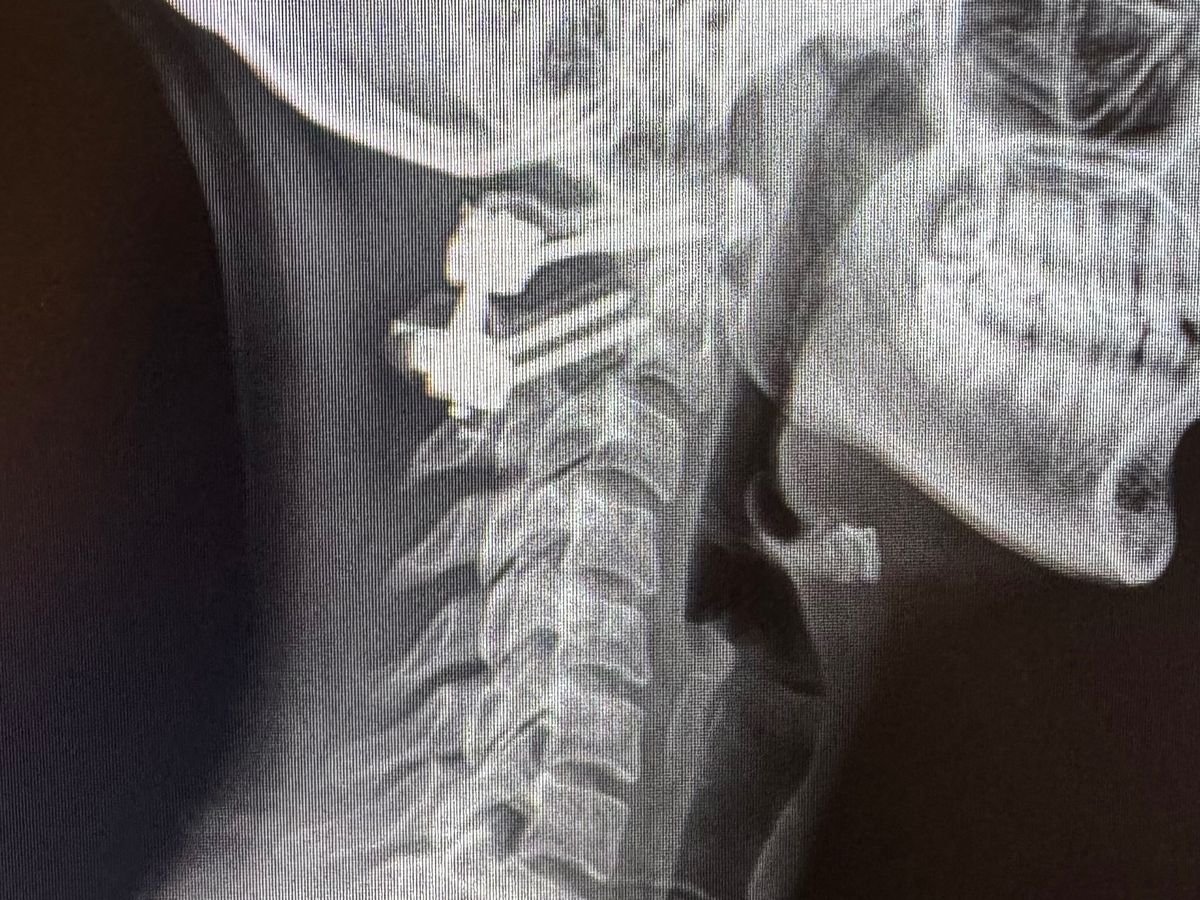

the crash broke my neck and my back, and I hit my head on my mirror and it cut my head open down to my skull. Luckily my kids were not injured.

i ended up needing surgery on my neck and now i have hardware in the area that likely has to stay in.. i also ended up needing to stay in an inpatient rehab for 2 weeks to learn to walk again and regain my strength due to damage to my nerves.